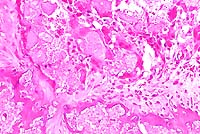

- Case 20-1. Bone. At the margin of the necrotic sequestra

(left), which extends through the growth plate, there is a mixture

of degenerate neutrophils, fibrin, edema, and cell debris (right).

10x

obj

- Case 20-1. Bone. The necrotic bone (right), and marrow

is being replaced by neutrophils, macrophages and fibroblasts

forming collagen (center & left).

- Microscopically, necrosis and fibrinopurulent debris

are prominent at the level of the distal growth plate of the

metacarpal bone. Mature and fragmented neutrophils are common,

fibrin thrombi are present in small blood vessels, and there

is widespread necrosis of cartilaginous, osseous, and myeloid

elements. Lesions extend into the epiphysis and diaphysis, and

occasional clefts are present in the growth plate cartilage.

The necrotic areas are poorly circumscribed by mononuclear leukocytes

and dense fibrovascular stroma. Microscopic findings in other

tissues included histiocytic foci (paratyphoid nodules) in the

liver and crypt abscesses in the ileum.